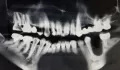

Недавно сделала рентген, на котором четко видно серое пятно в том месте, где, когда то была киста (на рентгене она была черная).

Прикрепленые фото

Ничего вам не вылечили, а причина данной ситуации в некачественном лечении каналов. Боль прошла лишь потому, что прошло обострение.

У вас именно киста и не питайтесь иллюзиями, данный зуб необходимо удалить, чтобы впоследствии было, куда ставить имплантат, так как мы все знаем, грануляция рассасывает костный объём.